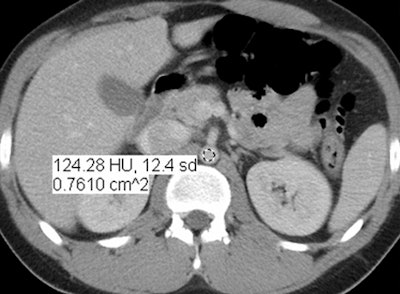

In an objective evaluation, reduced-dose MBIR images had decreased image noise compared with standard-dose 30% ASIR images (for example, 12.7 HU versus 19.4 HU in the aorta, respectively, and 8.7 HU versus 14.2 HU in the liver).